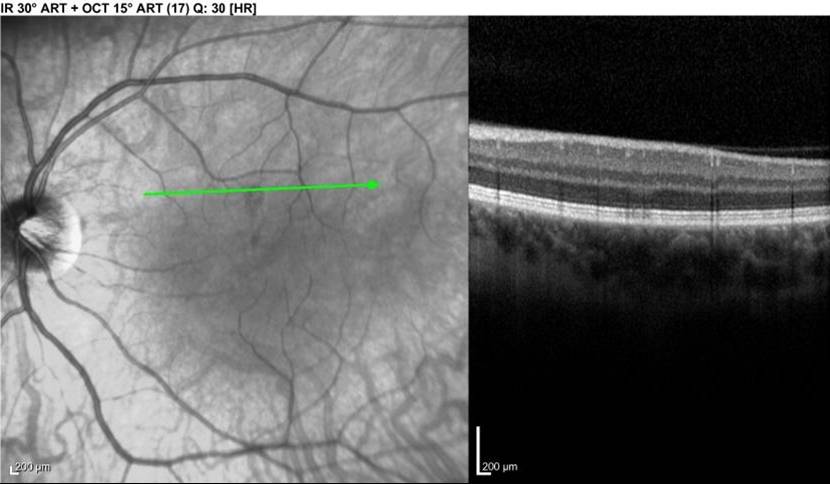

LEFT - Infrared view of left macula. Lesion is dark area at the middle of the green line. RIGHT - Focal signal reduction of the Inner Segment / Outer Segment junction within the lesion. The above lesion was NOT visible on funduscopic examination at the time of this photograph / OCT.

- Infrared fundus photography. SD-Optical Coherence Tomography (OCT) machines use infrared light to illuminate the macula for the photographer prior to any cross-sectional images being obtained. Lesions are visible as dark gray, petalloid, perifoveal lesions with the tip pointed toward the fovea. These correspond anatomically to the scotomas if the patient draws them on an Amsler grid or if they are documented via formal visual field testing.

- SD-OCT: Hyperreflective plaque is seen initially at outer nuclear (ONL) and outer plexiform layers of OCT, indicating disruption of photoreceptor cell bodies and their axons. Focal ellipsoid zone (EZ) disruption ensues. With time, EZ reconstitutes but persistent interdigitation zone disruption is noted. The hyper-reflective plaque fades away and is replaced with ONL thinning.